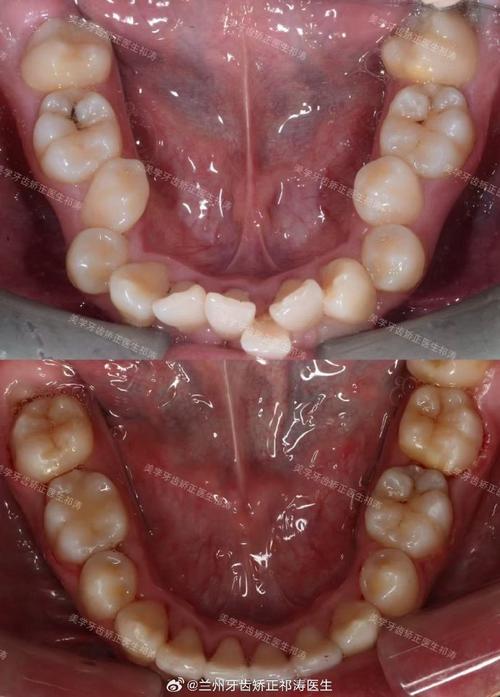

牙根裸露的本质是牙龈组织的退缩,使原本被牙龈包裹的牙根表面暴露出来,牙齿表面覆盖着一层牙釉质,是最坚硬的组织,但牙根表面覆盖的是牙骨质,下方连接着敏感的牙本质,一旦暴露,外界刺激(冷、热、酸、甜)容易通过牙本质小管传递至牙髓,引发敏感症状,在矫正牙齿时,牙齿需要在牙槽骨内移动,牙槽骨会随之发生改建——受压侧骨吸收,牵引侧骨增生,若矫正力度过大、移动速度过快,或患者自身牙槽骨条件较差(如骨量不足、骨质疏松),可能导致牙槽骨过度吸收,进而牵连牙龈组织,使其失去支撑而萎缩,形成牙根裸露。

除了矫正过程中的力学因素,其他原因也可能加剧牙根裸露,矫正前若存在未控制的牙周炎(牙龈炎进展到牙周组织感染),会导致牙槽骨 already 吸收,牙龈萎缩,此时矫正可能进一步加重问题;矫正期间口腔卫生维护不当,牙菌斑堆积引发牙龈炎症,长期炎症会破坏牙龈附着;个体差异(如天生牙龈薄、牙根形态异常)和不良习惯(如刷牙用力过猛、咬硬物)也是诱因。